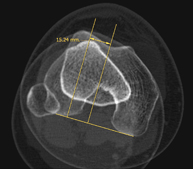

- Knee CT

Radiological examination based on an X-ray system and detectors that rotate around the patient, reconstructing the images by computer (multidetector computed tomography - MDCT) to study the bones, muscles and joints of the knees.

Exploració radiològica que mitjançant un sistema de raigs X i detectors que giren al voltant del pacient i que reconstrueixen les imatges per ordinador (TC Multidetector), permet l'estudi detallat dels ossos, els músculs i les articulacions del turmell i el peu. - TC d'estudi rotacional EEII (Bàscula rotuliana, distància TA-GT)

Exploració radiològica que mitjançant un sistema de raigs X i detectors que giren al voltant del pacient i que reconstrueixen les imatges per ordinador (TC Multidetector), permet calcular una sèrie de mesures a nivell de maluc, genolls i turmells per solucionar problemes de rotació i angulació de les extremitats inferiors. - TC d'ossos llargs